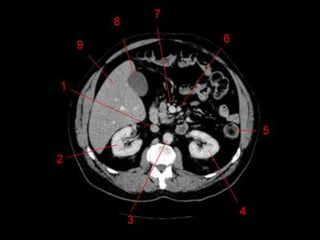

• Os oito segmentos são divididos:

– A primeira divisão é realizada dividindo através da

Porta Hepática, em esquerdo (I a IV) e direito (V a VIII)

– A divisão é feita baseada em um relógio

– Caudado é o segmento I

– No ‘lobo’ esquerdo, o IV separa-se do II e do III pela

veia hepática esquerda, representado

anatomicamente pelo ligamento falciforme.

– II e III se dividem através de uma linha imaginária

transversal na altura da porta hepática.

– No ‘lobo’ direito, se divide os segmentos através de

uma linha transversal e pela veia hepática direita.

Subdivisão Funcional

• Fundamental importância para Ressecção.

• Maioria das lesões são do fígado direito.

Subdivisão Funcional • Osoito segmentos são divididos: – A primeira divisão é realizada dividindo através da Porta Hepática, em esquerdo (I a IV) e direito (V a VIII) – A divisão é feita baseada em um relógio – Caudado é o segmento I – No ‘lobo’ esquerdo, o IV separa-se do II e do III pela veia hepática esquerda, representado anatomicamente pelo ligamento falciforme. – II e III se dividem através de uma linha imaginária transversal na altura da porta hepática. – No ‘lobo’ direito, se divide os segmentos através de uma linha transversal e pela veia hepática direita.

Subdivisão Funcional • Fundamentalimportância para Ressecção. • Maioria das lesões são do fígado direito.